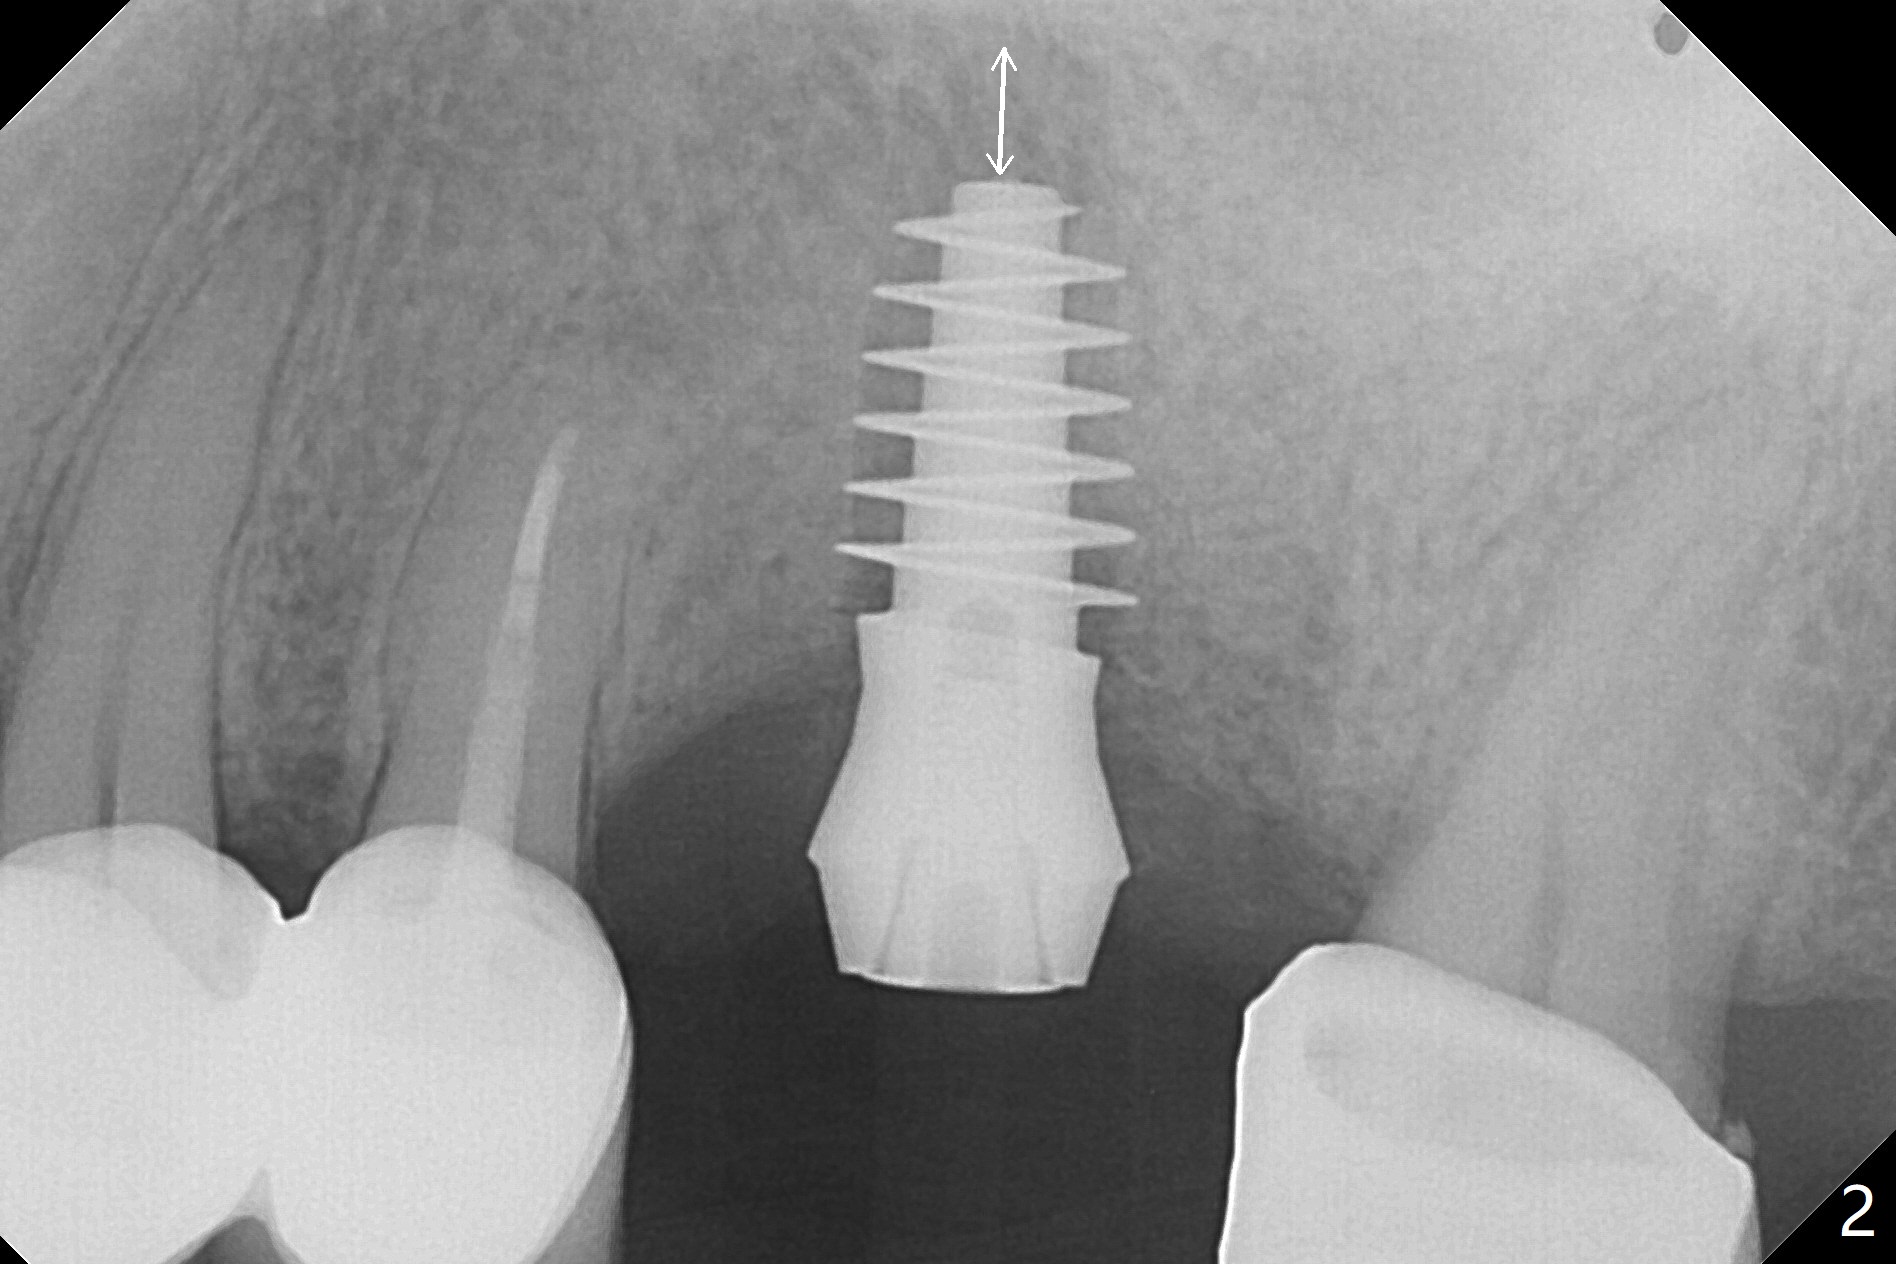

After 4.5x11.5 mm drill (10.5 mm offset) and 5.0 mm tap with guide at #14, the depth of the gingiva is measured 3 mm. A 5.5x9(3) mm Magicore cannot enter the green sleeve and is placed free hand (Fig.1). The margin is slight subgingival mesiodistal. With 3-4 turns, the buccal margin is slightly subgingival, while the palatal one slightly supragingival (Fig.2). The length of the implant could be 11 mm, considering the apical space (double arrows). To prevent periimplantitis, what is the appropriate placement depth coronally? Where does Titanium end? Dr. Wang thinks that the placement level is right. Probably due to underprep, the mesial crestal bone appears to have been resorbed 7 months postop (Fig.3 ^, as compared to Fig.1). The gingiva is healthy. A 4.3x5 mm solid abutment is torqued 20 Ncm for impression. The guide allows the implant to be placed lingual because of buccal concavity (Fig.4), but the coronal end of the solid abutment in the center for restoration (Fig.5 A). The crown is seated partially on the Magicore (M). The temp bond cemented crown is off 8 months post cementation (Fig.6). The bone density increases especially mesial.